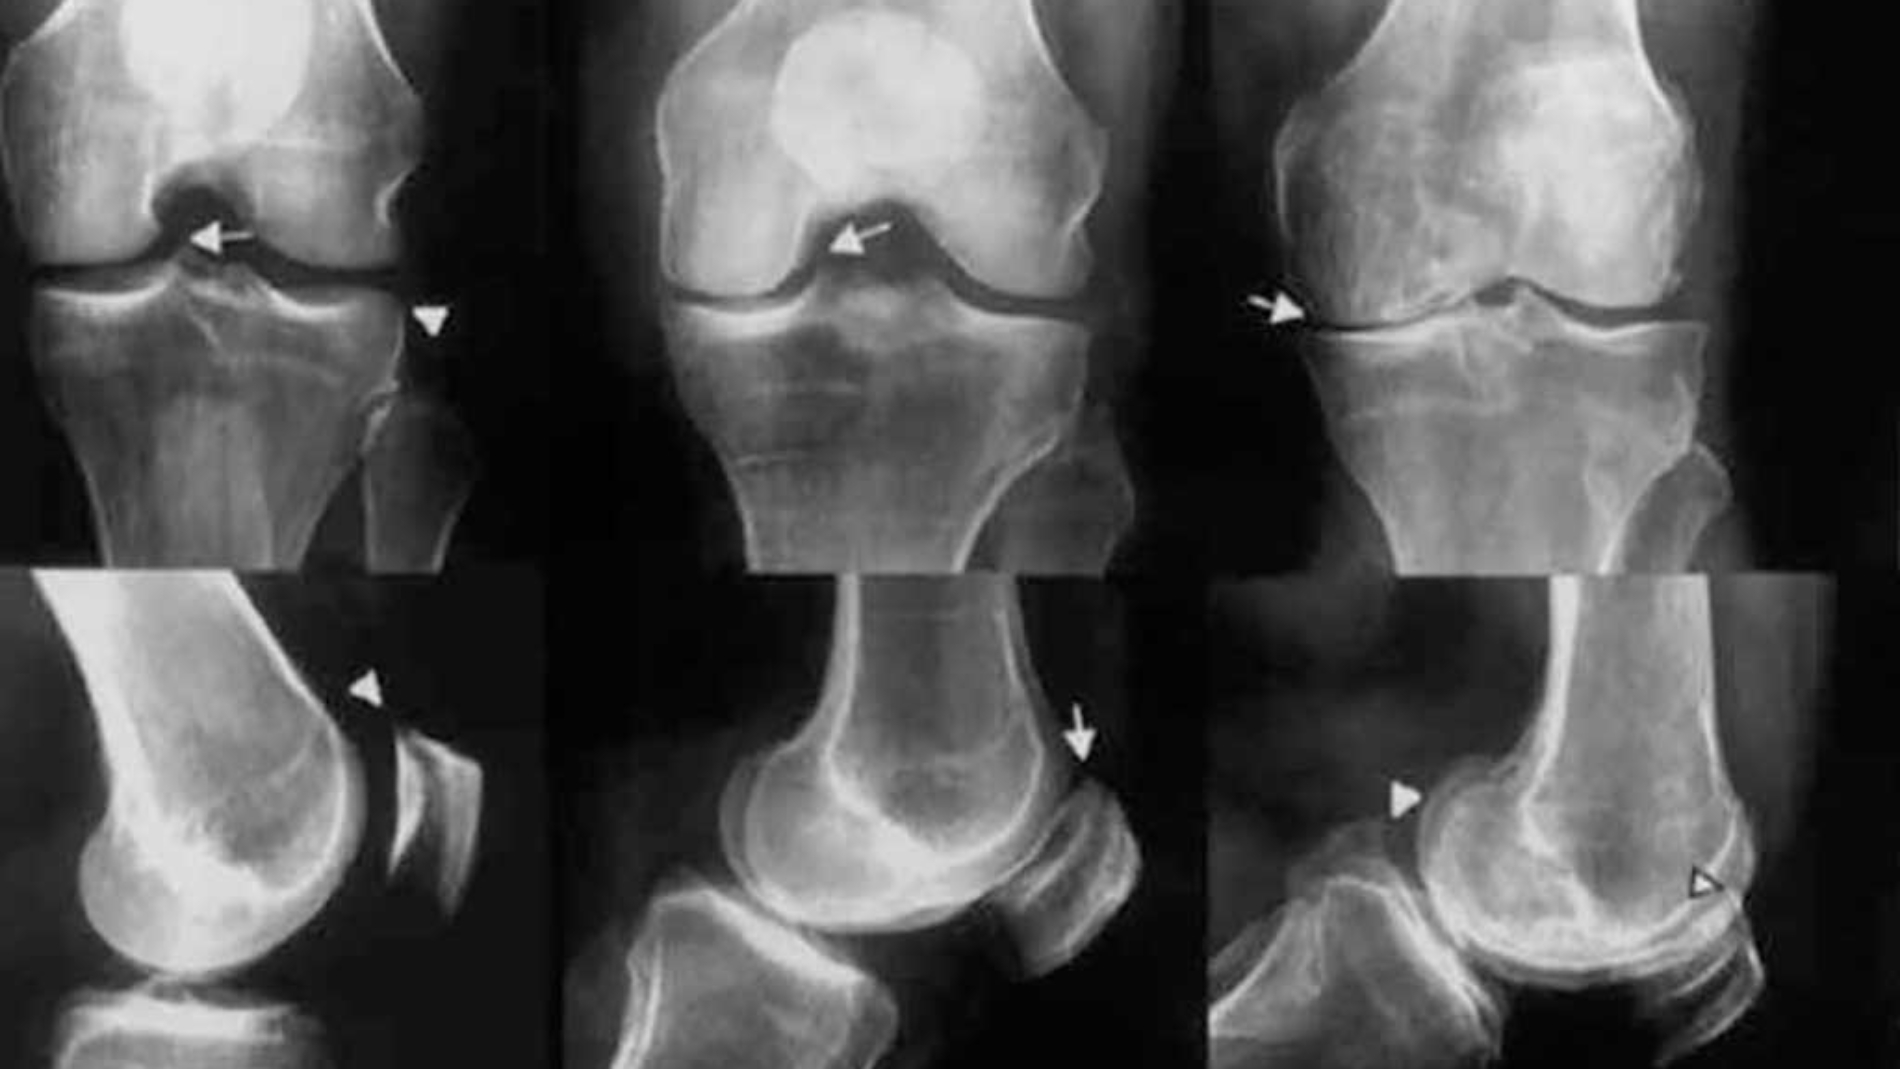

Príznaky sa neobjavia náhle. Mnohí pacienti najprv pociťujú stuhnutosť po prebudení alebo po dlhšom sedení. Nasleduje bolesť pri pohybe, obmedzený rozsah pohybu, opuchy či pocit „zasekávania“ kĺbu. V pokročilých štádiách môže artróza výrazne znížiť kvalitu života a obmedziť samostatnosť. Diagnóza sa potvrdzuje fyzikálnym vyšetrením, röntgenom, prípadne magnetickou rezonanciou. Liečba artrózy sa môže líšiť v závislosti na závažnosti symptómov.

V niektorých prípadoch sa robia aj krvné testy na vylúčenie zápalových reumatických ochorení.